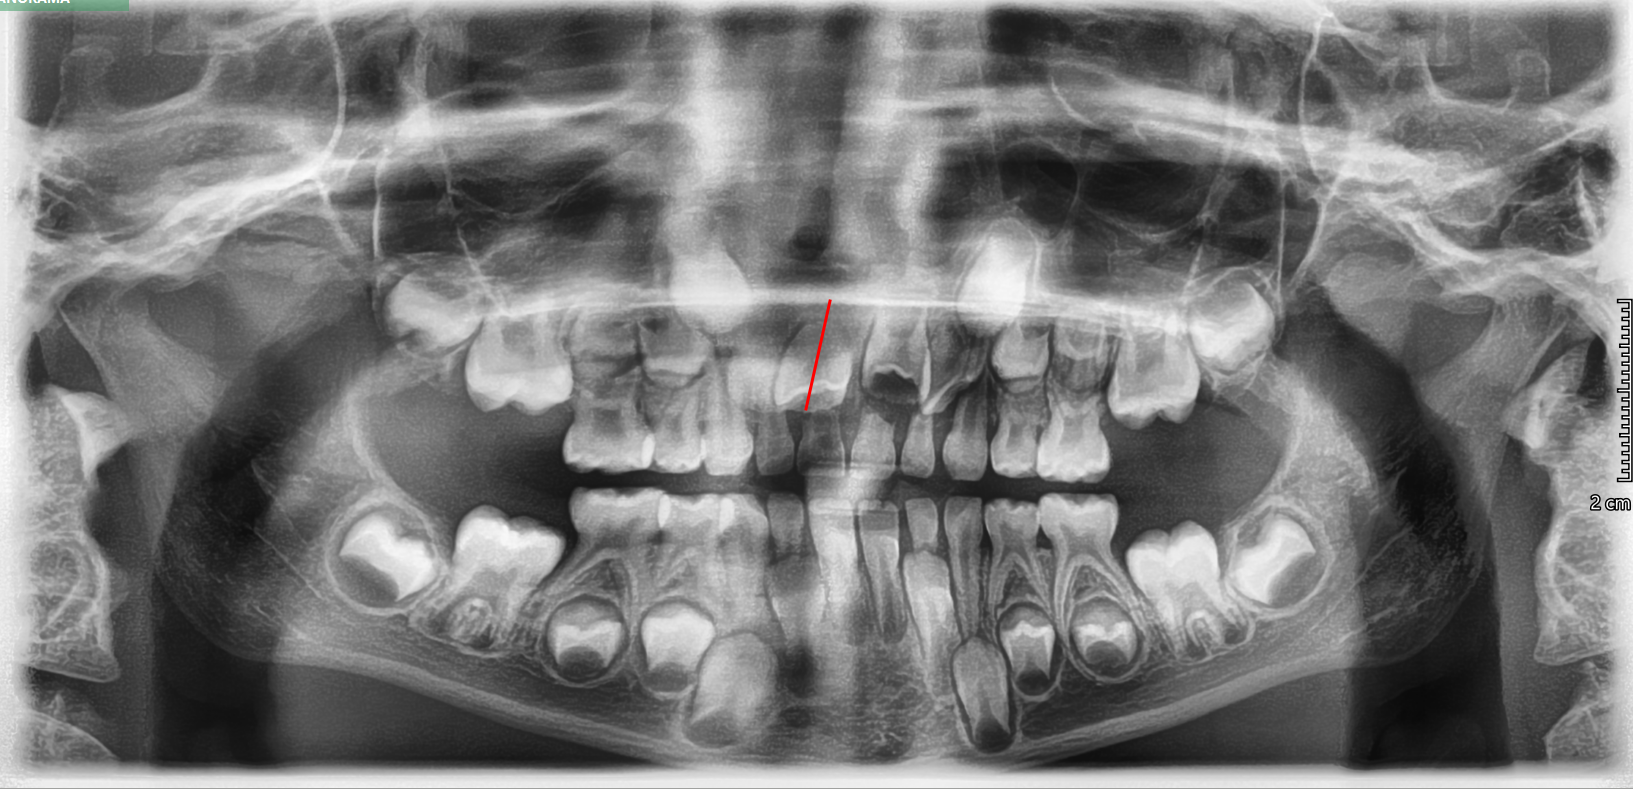

TREATMENT STARTED AT AGE : 7

- Myobrace K1 Small

- Mixed Dentition

- Class 2